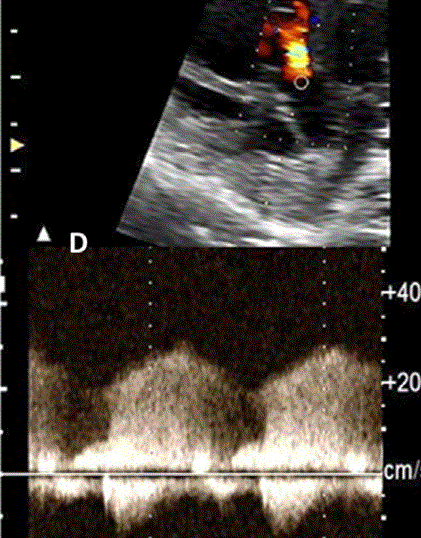

图27进展性主动脉狭窄。一例23周胎儿的严重主动脉狭窄,伴有扩张和低动力性左心室(LV)伴心内膜弹性纤维变性。(A) 彩色多普勒显示,主动脉瓣(箭头)开始出现花彩血流(左),频谱多普勒显示阶差为 25 毫米汞柱(右(B) 二尖瓣(MV)流入是单相的,持续时间短(左),二尖瓣反流提示左心室收缩压高(46毫米汞柱压力梯度加左心房压力;右图)。(C)存在逆行主动脉弓流(红色,左)和左至右心房流(红色、右)是预测由于通过左心的流量减少而在妊娠期间发展的进行性左心发育不全的额外发现。(D)LV逐渐变为球状,长度缩短,到36周时不再形成心尖。